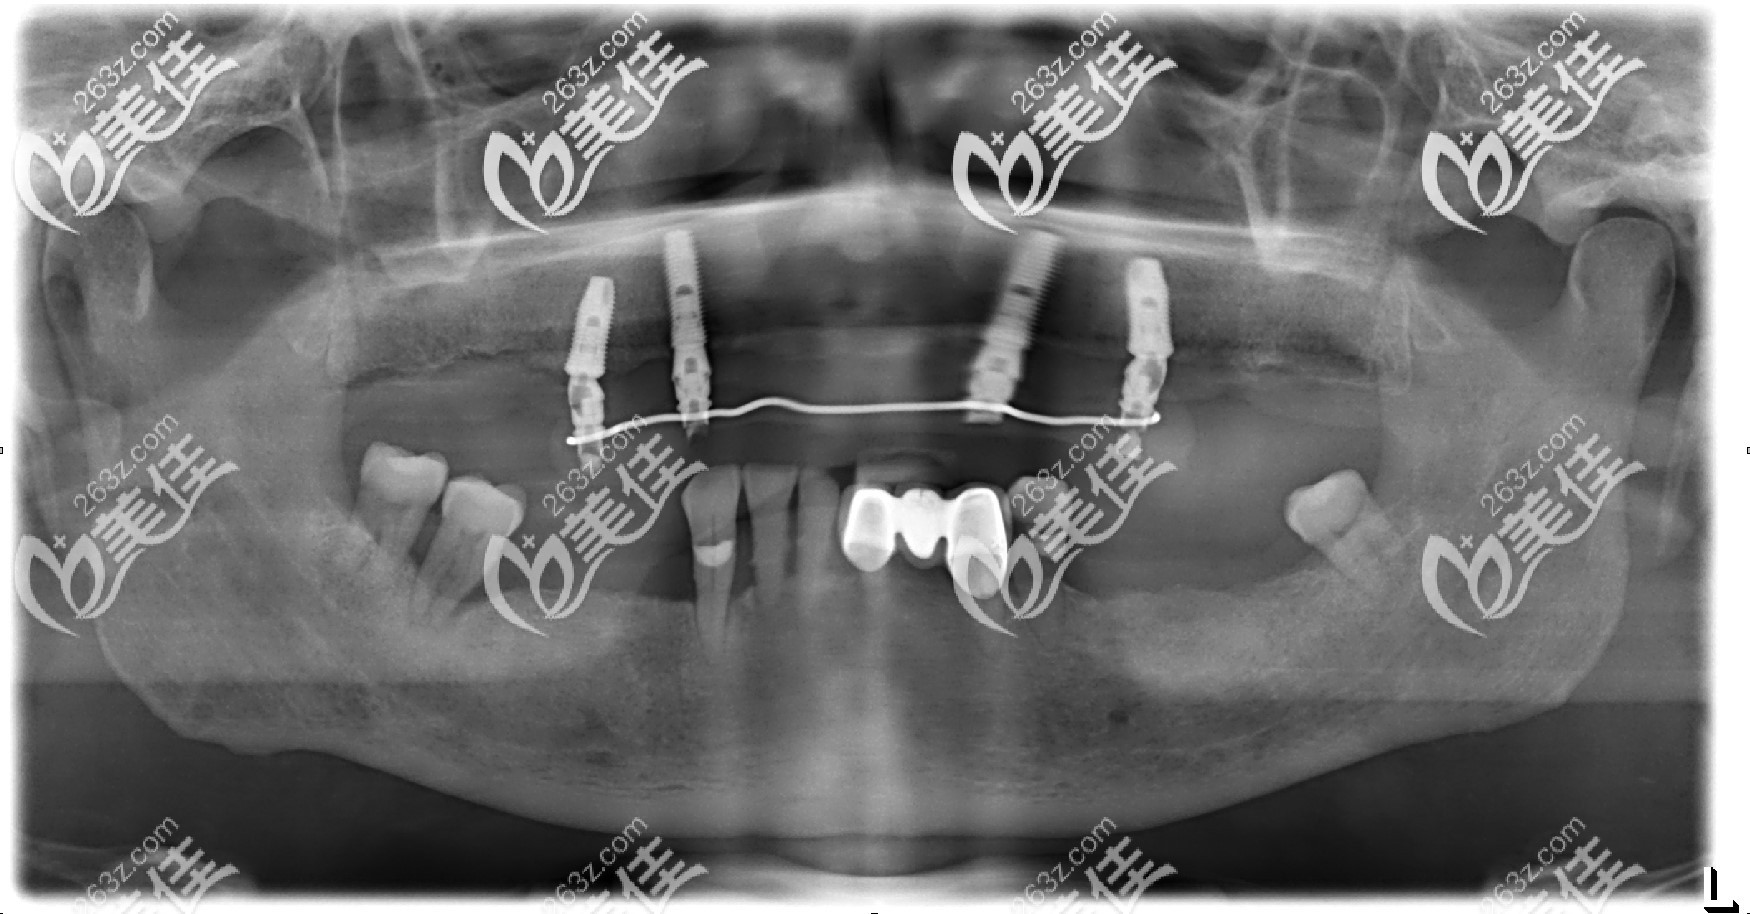

老爸种牙后的拍的片子▼

allon4种植牙弊端:

①因为是斜着植入的种植体,所以对医生的技术要求很高,如果植入轨道不对,后期失败率很大;

②另外就是斜的种植体承重能力比直着种入的植体稍微差点。

不过老爸选的是诺贝尔的种植体,相当于种植体中的航母,这点不足足可以弥补,再加上林医生也做过种植案例,技术上也让人放心。